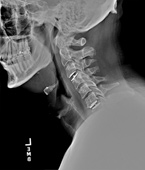

Before

After